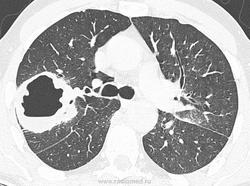

Я,конечно,не КТолог,и в реальности КТ видела меньше,чем на сайте)) Но есть полость с неравномерными по толщине стенками,с бухтообразно подрытыми внутренними контурами, наружние контуры практически на всем протяжении четкие,легочная ткань,наверно,не изменена.Rg-признаки периферического с-r с распадом

Туберкулезная каверна в S3? Утолщение междолевой щели слева - перисциссурит?

бронх не показали, сосуды не убедительно...+1 tbs каверна?

на туберкулёзную каверну.

если это каверна - то где фон? Больше.. за с-r...

А, на абсцесс не тянет?

тянет на абсцесс. И на каверну. На рак не тянет. А кровохарканье или симптомы какие?

Кровохарканья нет. По всей видимости, таких размеров "каверкот" все вокруг бы "заплевал", в плане окружающей легочной ткани?

Здесь вопрос в чём-если полость дренируется -это не рак. Если не рак то либо каверна; либо абсцесс.

Предыдущий случай - хронический абсцесс,  прооперирован.